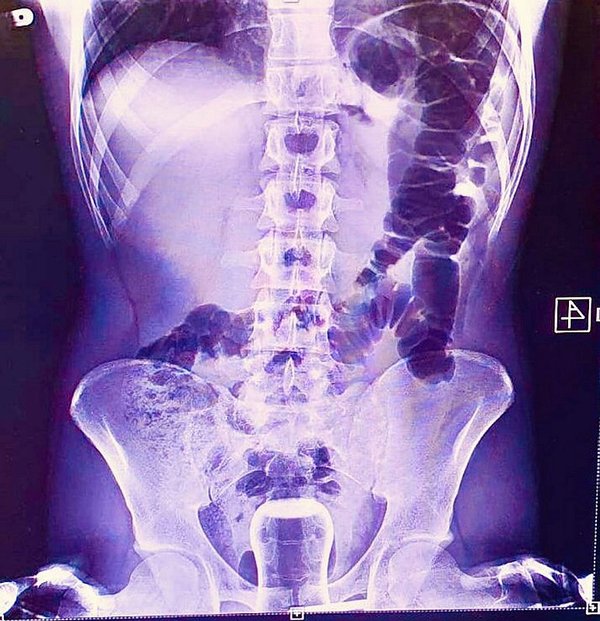

Geçen cuma günü ismi açıklanmayan bir kişi Mehmet Akif İnan Eğitim ve Araştırma Hastanesin'e başvurdu. Acil serviste hastanın çekilen röntgeninde anüs bölgesinde çay bardağı görüldü. Bu kişi genel cerrahi servisinde ameliyata alındı. Çay bardağı, uzman doktorlar tarafından gerçekleştirilen operasyonla çıkarıldı.